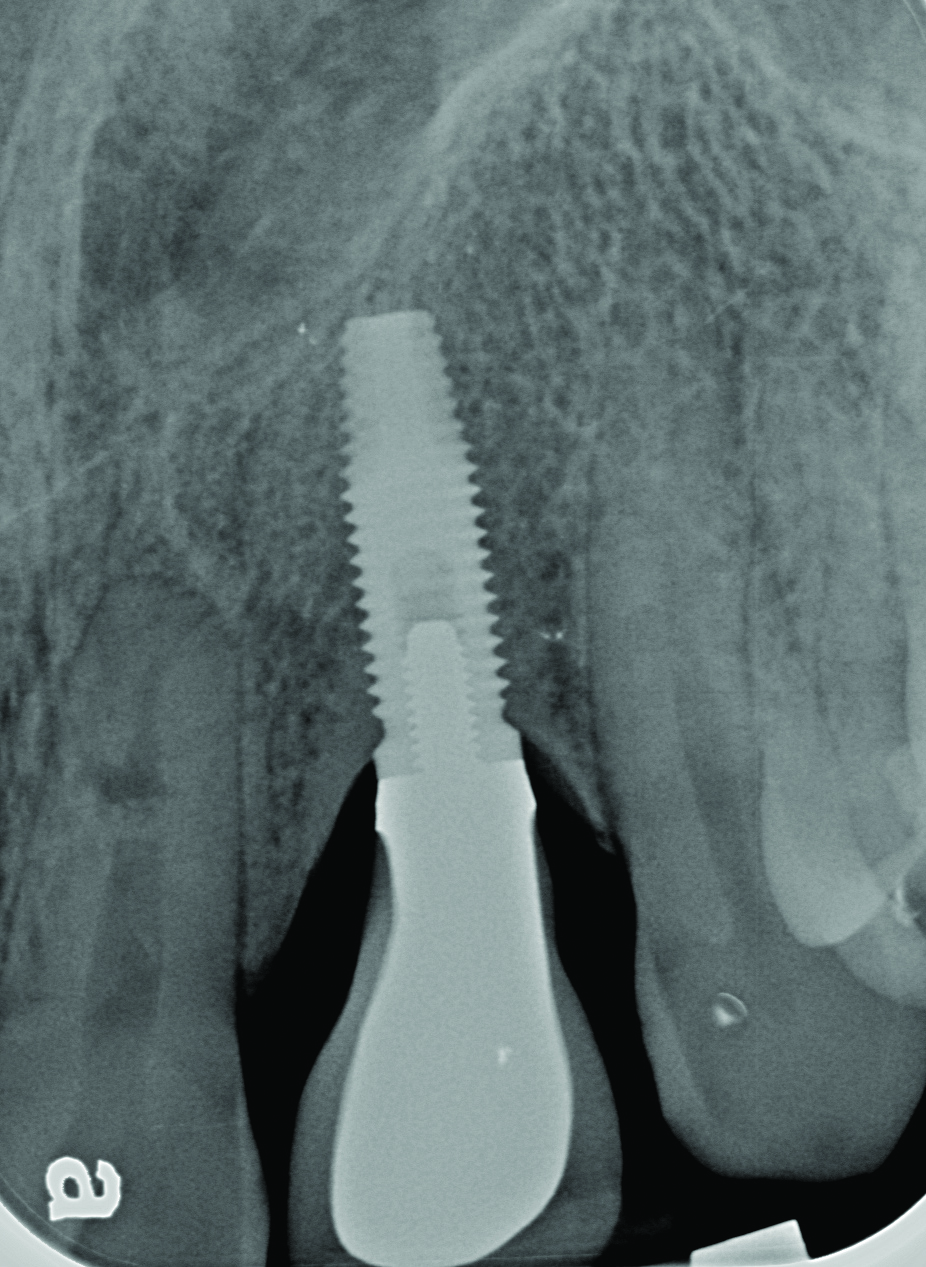

Peri-implant diseases present in two forms—peri-implant mucositis (Figure 1 and Figure 2) and peri-implantitis (Figure 3 and Figure 4). Both involve an inflammatory reaction in the tissues surrounding an implant—ie, bleeding on probing and/or suppuration; probing depths usually exceed 4 mm.1,3 However, when there is also bone loss present beyond the physiologic remodeling that may occur after implant placement, a diagnosis of peri-implantitis should be made, as this condition, when compared to mucositis, is far more serious and difficult to resolve.4

Radiograph of this same area. Note that there is no indication of bone loss and a long abutment collar. Hence, the diagnosis of peri-implant mucositis is given.

Figure 2